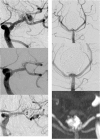

Introduction: The Neuroform Atlas Stent System is a recently introduced modification of the original Neuroform Stent System consisting of a hybrid design with open and closed cells. Initial experience, technical considerations and treatment outcomes including 1-year follow-up using the Atlas stent in combination with coil embolization are reported.

Material and methods: Thirty patients with 30 unruptured aneurysms were treated with stent reconstruction. Immediate, 4-month and 12-month post-treatment angiography and clinical assessment were performed.

Discussion: In 29 cases, the stents were delivered and positioned without difficulty in deployment. Technical complications occurred in one patient related to advancement of the stent during delivery. One procedure-related clinical complication occurred with no permanent neurological deficit. On immediate post-treatment angiography, 29 of 30 aneurysms showed Raymond Class I or Class II occlusion. At 1-year follow-up, all 30 patients were clinically stable and 18 of 30 aneurysms showed Raymond Class I complete occlusion. Retreatment was performed in two patients with residual aneurysm.

Conclusions: The Atlas stent is technically safe and simple to implant and has a low thrombogenic potential. We experienced fewer problems associated with deployment and implantation, thromboembolic complications and hemorrhagic events compared with other types of stents, including braided stents. However, because of its low thrombogenic potential, partially occluded aneurysms or those with aneurysm remnants do not progress to complete occlusion.